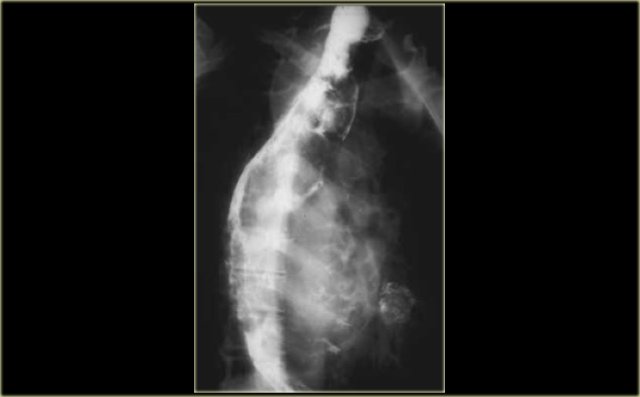

They are often bulky but nonobstructive as in the case on the left.

Leiomyosarcomas and rare primary melanomas of the esophagus also tend to be bulky but do not cause significant obstruction.

On the left a patient with a leiomyosarcoma of the esophagus.

Margin (arrows) of bulky lesion visible on chest radiograph.

Lateral view of esophagram shows marked irregularity and esophageal narrowing (arrows).

On the left another patient with a leiomyosarcoma of the esophagus.

Large lesion distorts esophageal lumen.

CT shows lesion distorting but not obstructing esophageal lumen (arrow).